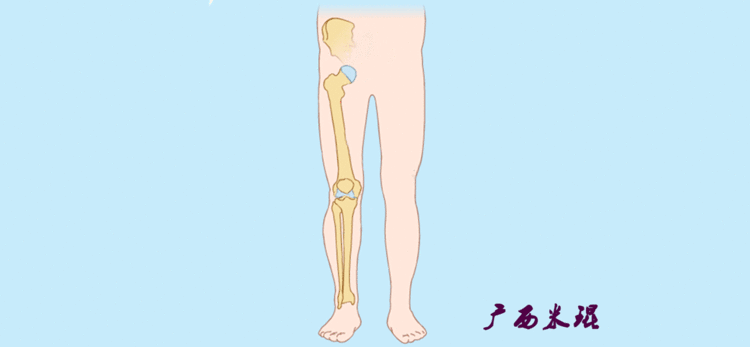

1、判定有无畸形下肢的畸形定义为生理轴线的偏移。关节角和轴线在冠状面、矢状面和横断面上可发生病理改变,并引起整个下肢的对线异常。

最常见的下肢畸形发生于冠状面,即膝内外翻畸形,冠状面的对线异常通过应用“对线异常检验”进行分析,机械轴的偏移(MAD)表现为对线异常。

膝内翻是指下肢力线通过膝关节中心点内侧,距中点2mm以上,偏内超过15mm为显著膝内翻。膝外翻是指下肢力线通过膝关节中心点外侧,距中点2mm以上,偏外超过10mm为显著膝外翻。

2、判断畸形的部位画出下肢全长片中的机械轴和力线轴,确定畸形来自股骨、胫骨还是关节内。首先我们确认股骨机械轴及mLDFA,超出范围为股骨畸形;然后我们确认胫骨机械轴及MPTA,超出范围为胫骨畸形;最后我们确认关节线的汇聚关系JLCA,超出范围为关节内畸形。